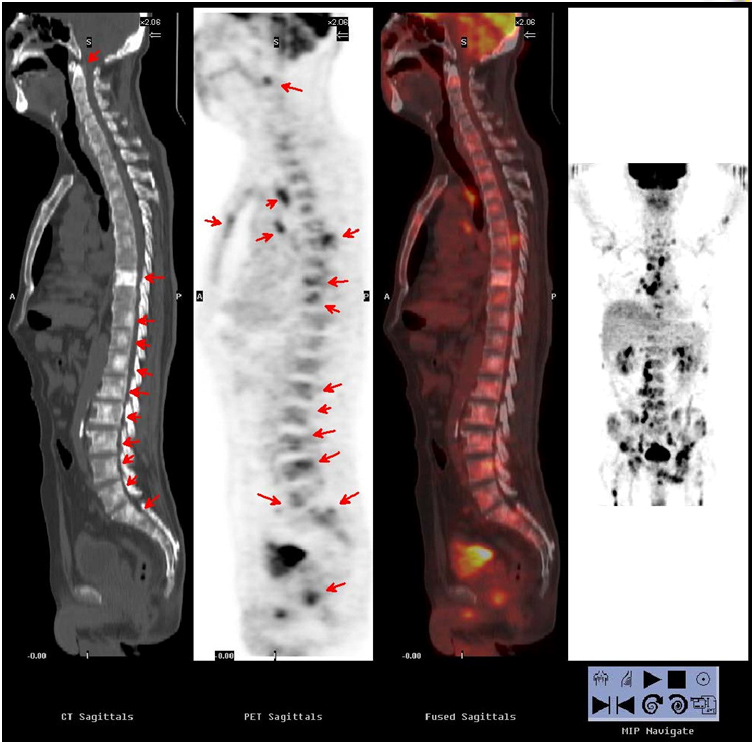

| 男,63歲,間斷低熱,檢查發(fā)現(xiàn)左肺下葉近胸膜處小結(jié)節(jié)影,臨床難以定性。PET/CT示前列腺局部葡萄糖代謝增高,伴全身多發(fā)骨髓和骨骼代謝增高。病理證實為前列腺癌。 |

| 腫瘤全身分期 |